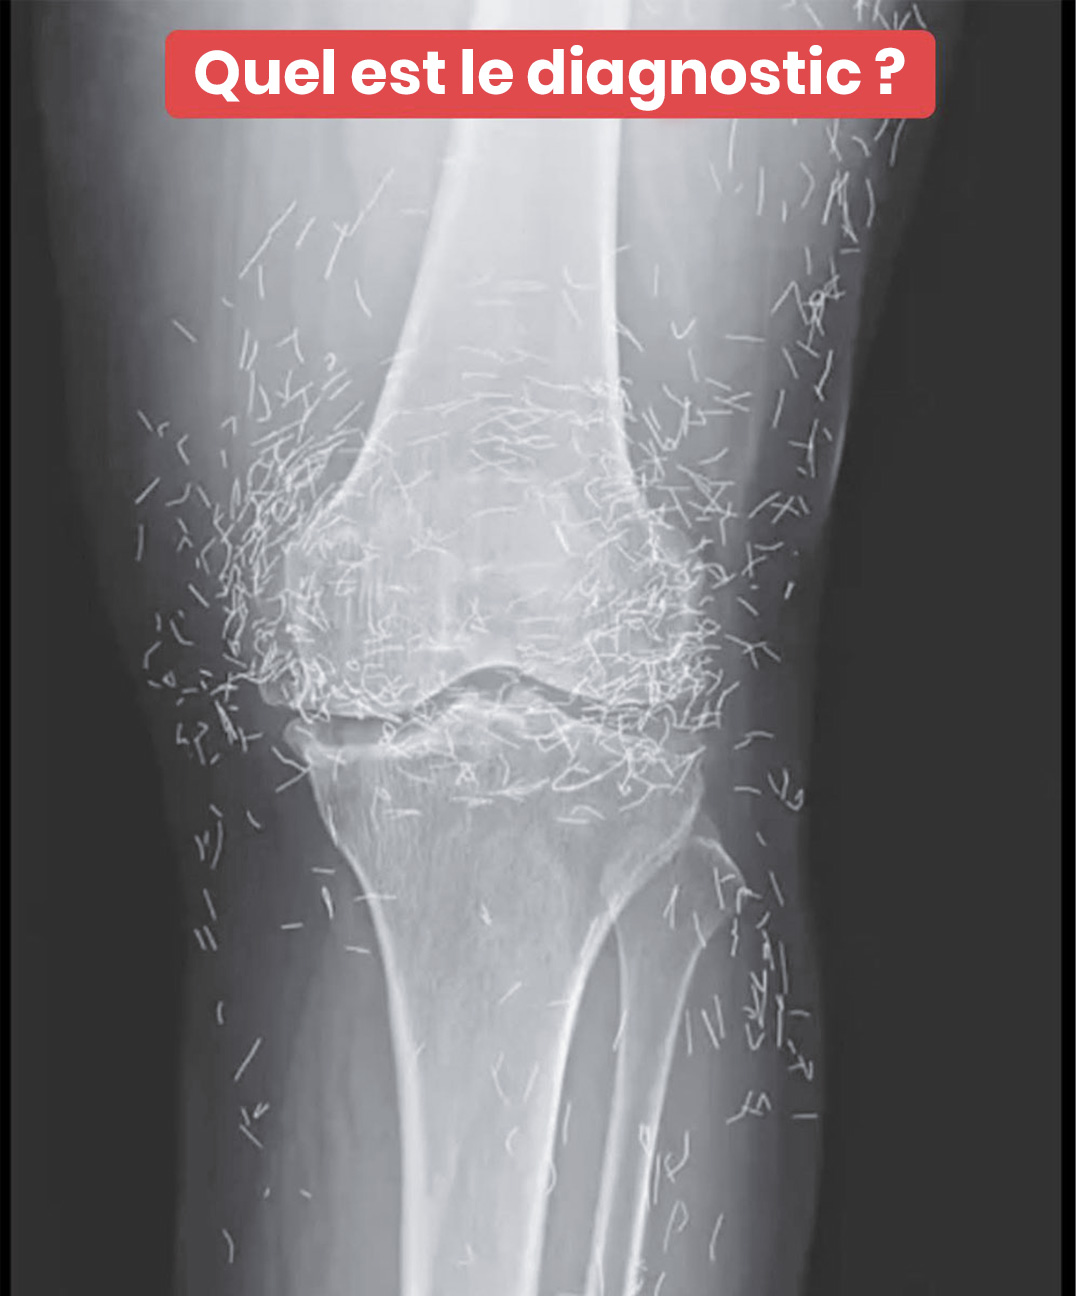

C’est lors d’un examen radiologique standard que l’équipe soignante a découvert, surprise, des centaines de petites aiguilles brillantes dispersées autour de ses genoux. Une véritable rareté clinique qui a suscité autant d’émerveillement que de prudence. Bien que l’or soit un métal inerte généralement bien toléré, la présence prolongée d’éléments étrangers n’est jamais sans conséquences.

D’après des spécialistes en imagerie, ces aiguilles peuvent masquer certaines zones sur les radiographies, rendant plus difficile le repérage d’autres pathologies. Surtout, elles compliquent la réalisation d’une IRM : le risque que les aiguilles bougent sous l’effet magnétique est réel, avec un potentiel de blessure des tissus proches.